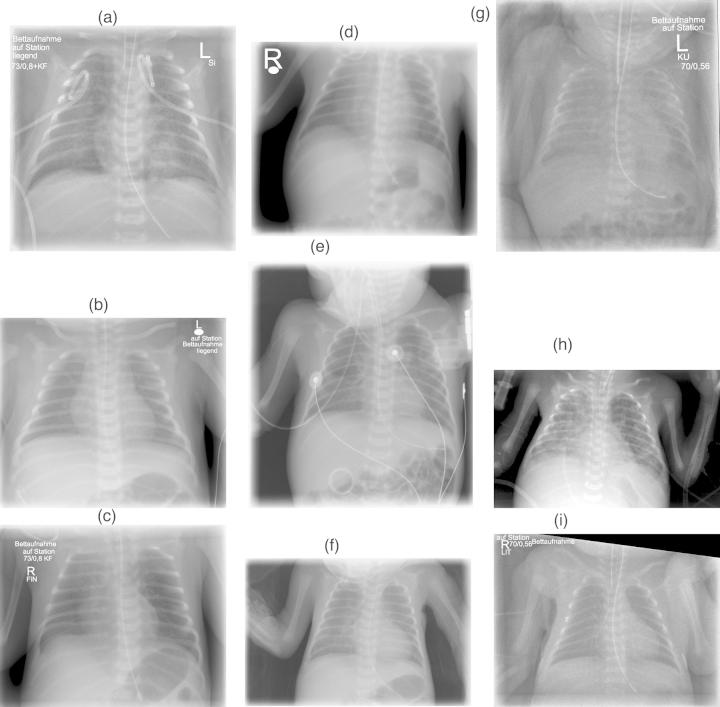

Unnecessary exposure of the abdomen, arms or head may lead to a substantial increase of the radiation dose in portable chest X-rays on the neonatal intensive care unit. The objective was to identify potential factors influencing inappropriate exposure of non-thoracic structures in two teaching hospitals.

The study analysed 200 consecutive digital chest radiographs in 20 preterm neonates (mean gestation 25 ± 1 weeks). Demographical data, tube settings and exposure parameters were recorded. To grade the collimation, we used a scoring system with a maximum of 12 exposed non-thoracic structures. Length of gestation, age, the radiographer, years of experience in performing X-rays and the number of in situ catheters or lines, were correlated with collimation quality.

There was no significant difference between the rates of optimal images obtained in the two hospitals (0.32 vs 0.39, n.s.). Scores showed that most suboptimal images had only mildly reduced image quality (1.40 ± 1.38 vs 1.20 ± 1.43, n.s.). Length of gestation or presence of surgical drains, catheters and tubes had no obvious effects on the exposure of non-thoracic structures. Large intra-individual variation in optimal collimation (14-86%) was noted for the radiographers in both hospitals; this was unrelated to their respective years of experience.

In our study, the only identifiable factor influencing the collimation of portable chest radiographs in preterm infants was the radiographer's dedication and awareness. There were no apparent differences between the hospitals investigated. Exposure of non-thoracic structures was relatively frequent and mainly involved the proximal humeri.

在新生儿重症监护病房进行便携式胸部X光检查时,不必要地暴露腹部、手臂或头部可能会导致辐射剂量大幅增加。本研究的目的是确定两家教学医院中影响非胸部结构不适当暴露的潜在因素。

该研究分析了20名早产儿(平均孕周25±1周)连续的200张数字化胸部X光片。记录人口统计学数据、管电流设置和曝光参数。为了对准直情况进行评分,我们使用了一个评分系统,最多可记录12个暴露的非胸部结构。孕周、年龄、放射技师、进行X光检查的年限以及体内导管或管路的数量与准直质量相关。

两家医院获得的最佳图像比例之间没有显著差异(分别为0.32和0.39,无统计学意义)。评分显示,大多数次优图像的图像质量仅略有下降(分别为1.40±1.38和1.20±1.43,无统计学意义)。孕周或手术引流管、导管和管路的存在对非胸部结构的暴露没有明显影响。两家医院的放射技师在最佳准直方面都存在较大的个体差异(14 - 86%);这与他们各自的工作年限无关。

在我们的研究中,影响早产儿便携式胸部X光片准直的唯一可识别因素是放射技师的专注度和意识。所调查的医院之间没有明显差异。非胸部结构的暴露相对频繁,主要涉及近端肱骨。